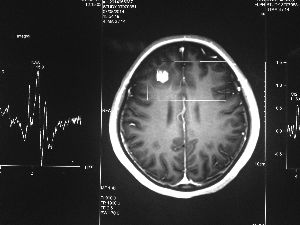

方框亮點為CT片顯示的異物

今年6月份,張敏在宿舍休息時,又發(fā)起了癲癇,也是口吐白沫,渾身抽搐。送到蘇州一家大醫(yī)院,頭顱核磁共振檢查出,張敏大腦右額葉處有一處病灶,也就是大腦額頭處有個東西。

腦袋里的東西,到底是腫瘤還是其他什么東西,這個謎像個石頭一樣,壓得張敏一家人喘不過氣。7月份,張敏一家又來到南京腦科醫(yī)院求醫(yī),第三次檢查后,醫(yī)生覺得很像是寄生蟲。不過,影像的檢查,只能作為醫(yī)生推測的依據(jù),具體是什么,只有手術(shù)拿出來后才能知道。